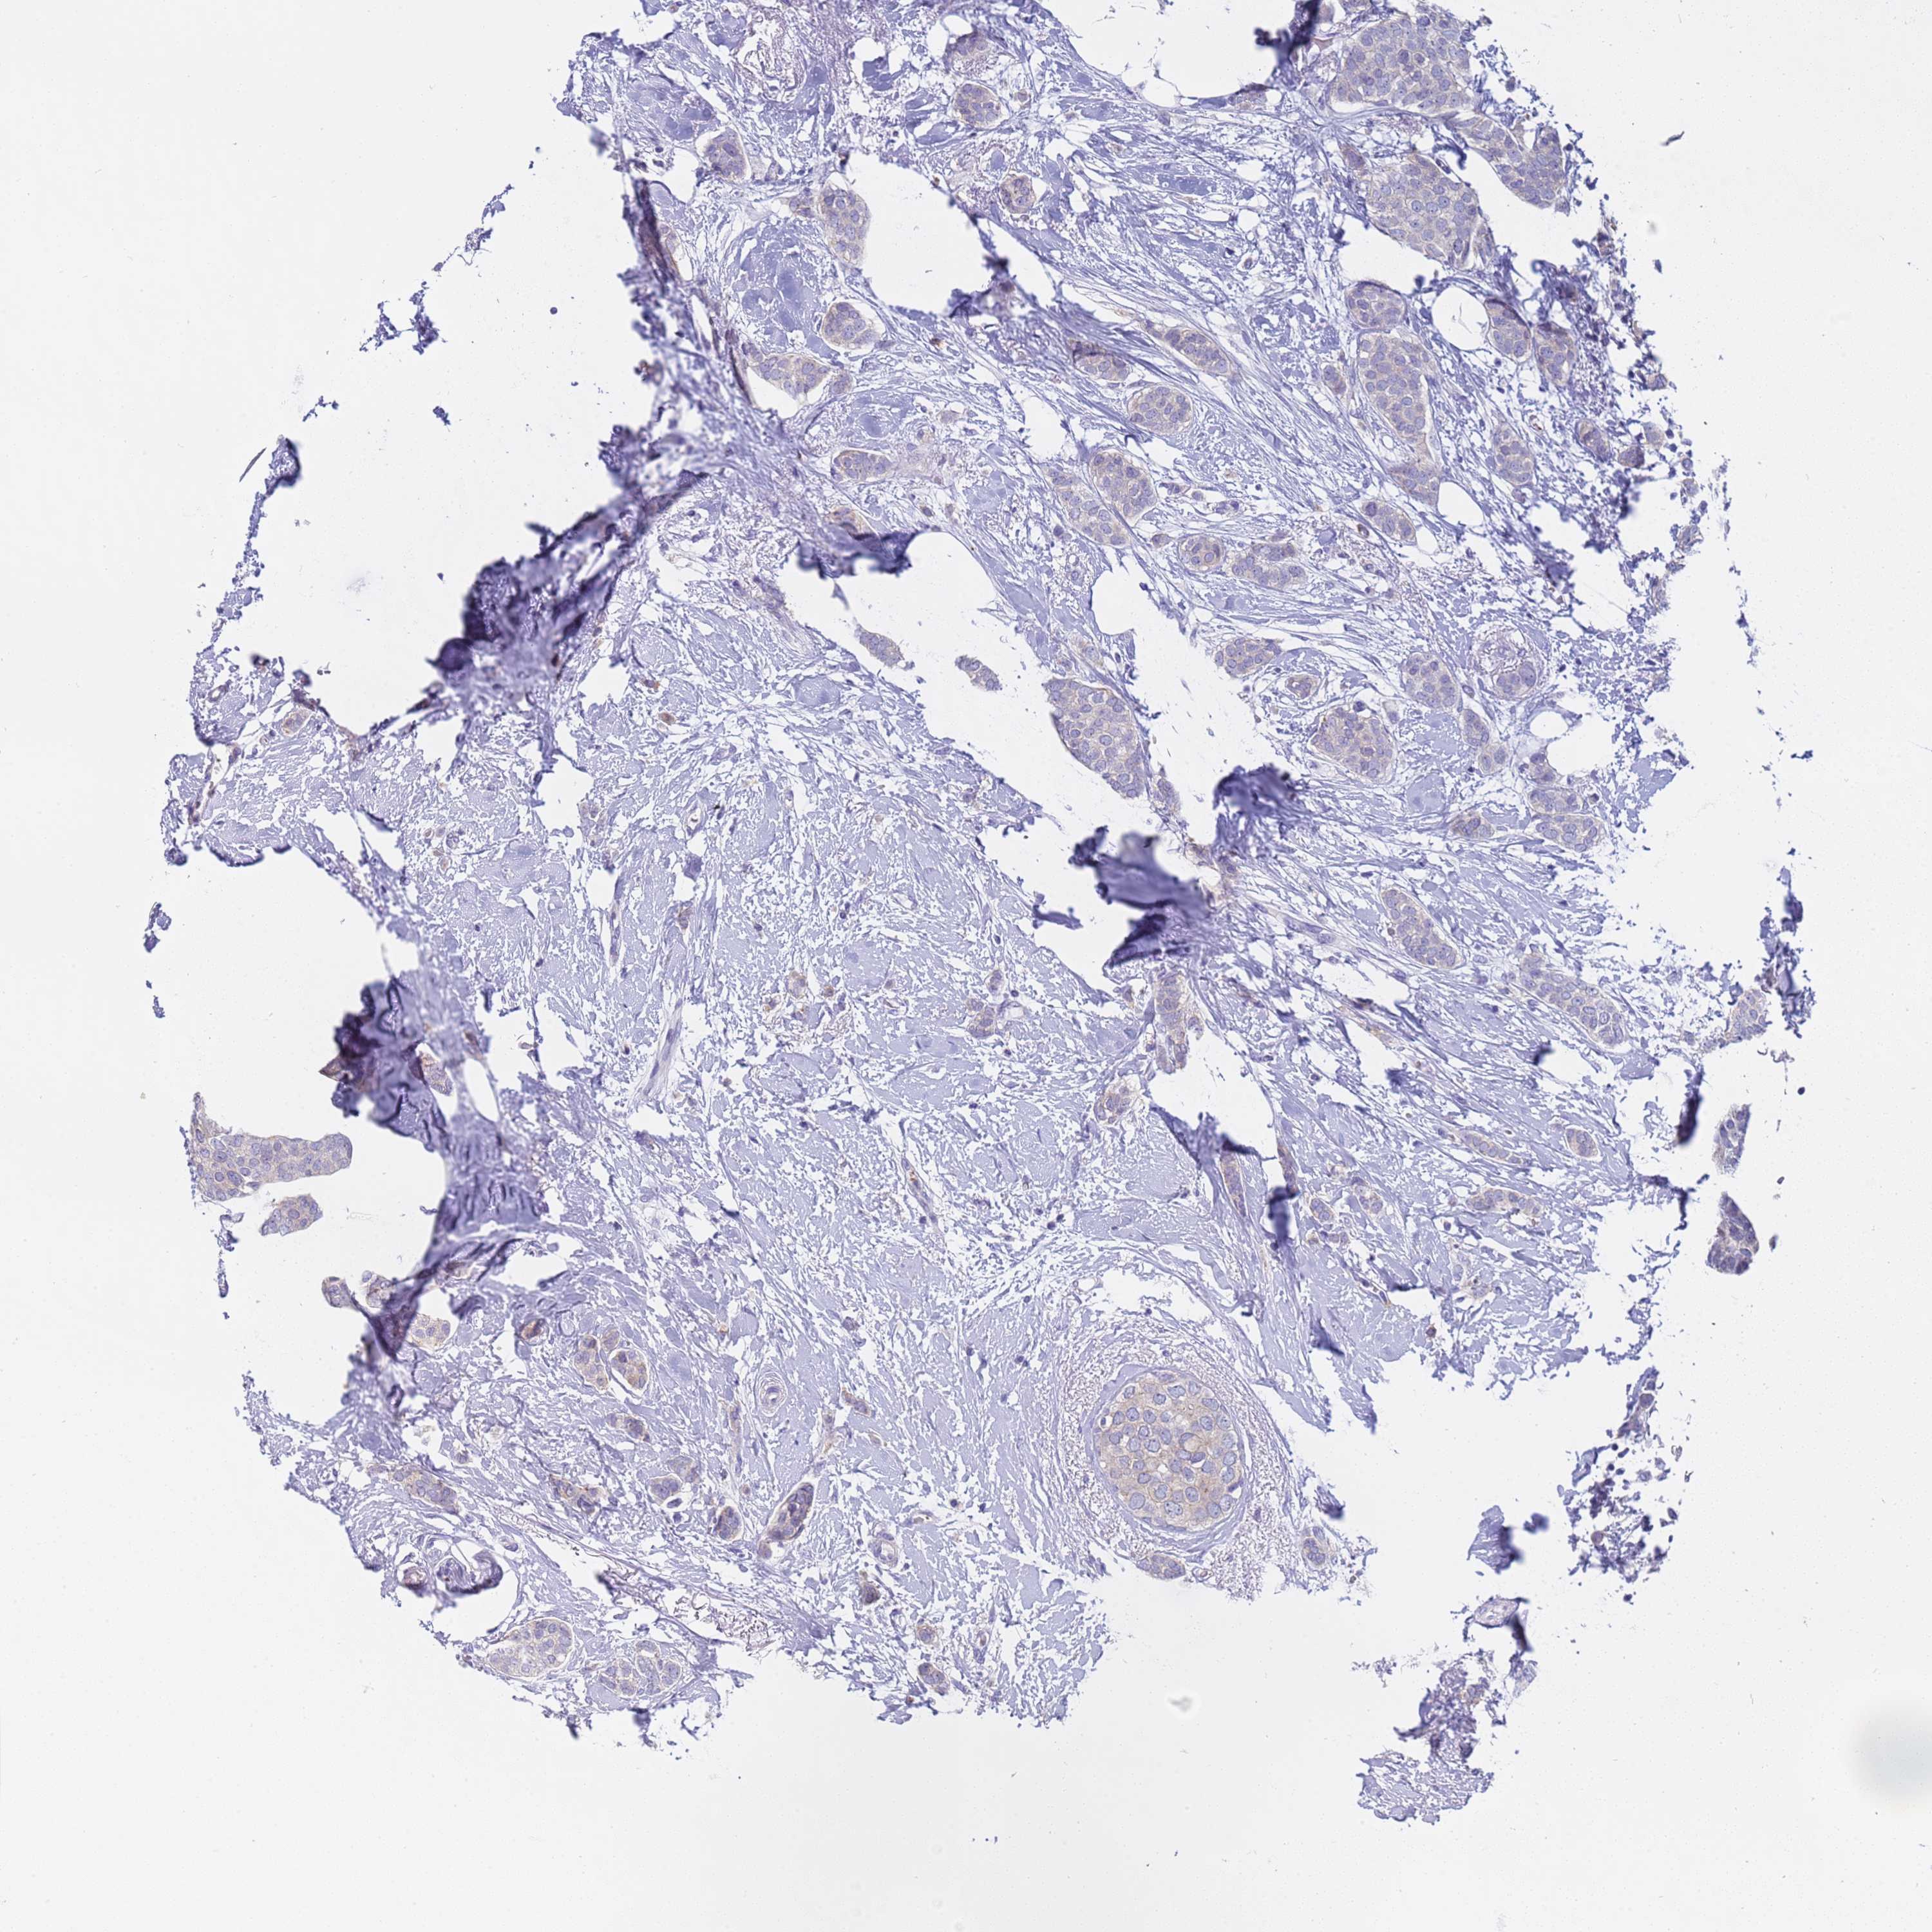

CANCER BREAST CANCER Show tissue menu

BRCA TCGA BRCA VALIDATION PROTEIN EXPRESSION

Breast cancer

Human cancer

Breast invasive carcinoma